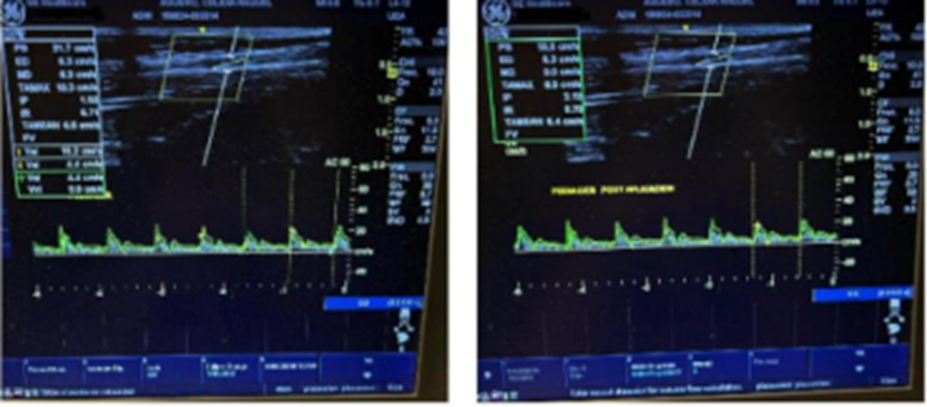

The patients underwent an arterial and venous Echo Doppler before and after the first application to rule out arterial involvement and to observe any changes in stroke flow at the microcirculatory level. We evaluated

onthe other hand, the patientmanifests clear improvement in the appearance of nutrition, turgor, and elasticity of the ulcer in the skin around the ulcer. It should be noted that studies were carried out with high-resolution Doppler echo and general equipment electric versant balance, in which an increase in peak arterial flow was observed in images.

Peak systolic flow increases artery pedia by 3% immediately after the first application of the CO2 transdermal gel. “Peak systolic velocity (PSV) is an index measured in spectral Doppler ultrasound. On a Doppler waveform, the peak systolic velocity corresponds to each tall “peak” in the spectrum window.”

Female 76, overweight, BMI 26, hypothyroidism, arterial hypertension, ulcer 5 cm long by 1.5 cm wide, bed with fibrin, surrounded by ochre dermatitis and stiff skin. Oral medication such as Diosmin, local collagenase cream, and elastocompression are indicated. The Doppler echo report shows positive arterial pulses and a 3% increase in the systolic peak immediately after applying the gel with CO2 transdermal.

Doppler ultrasound shows the insufficiency of the postphlebitic left popliteal vein in the venous system and increased 3% arterial flow after the first application of CO2 gel.

Venous vascular Doppler ultrasound, popliteal vein insufficiency, left the internal saphenous, positive arterial system, and increased systolic peak (1.3%) after the first application of CO2 gel.

In all cases, a Venous and Arterial echo Doppler were performed before and after the first application. The Venous Doppler showed different gradations or manifestations of chronic venous insufficiency, such as edema, reflux, and chronic DVT.

The Arterial Doppler done after the immediate application of the gel showed an increase in the peak stroke flow. The rise in blood flow consequently increased the oxygenation of the compromised tissue perfusion.

Notably, there were enhancements in the post-immediate arterial Doppler after the use of the combination of gels that produce CO2. There was an average increase in the systolic peak between 1.5 to 3%.